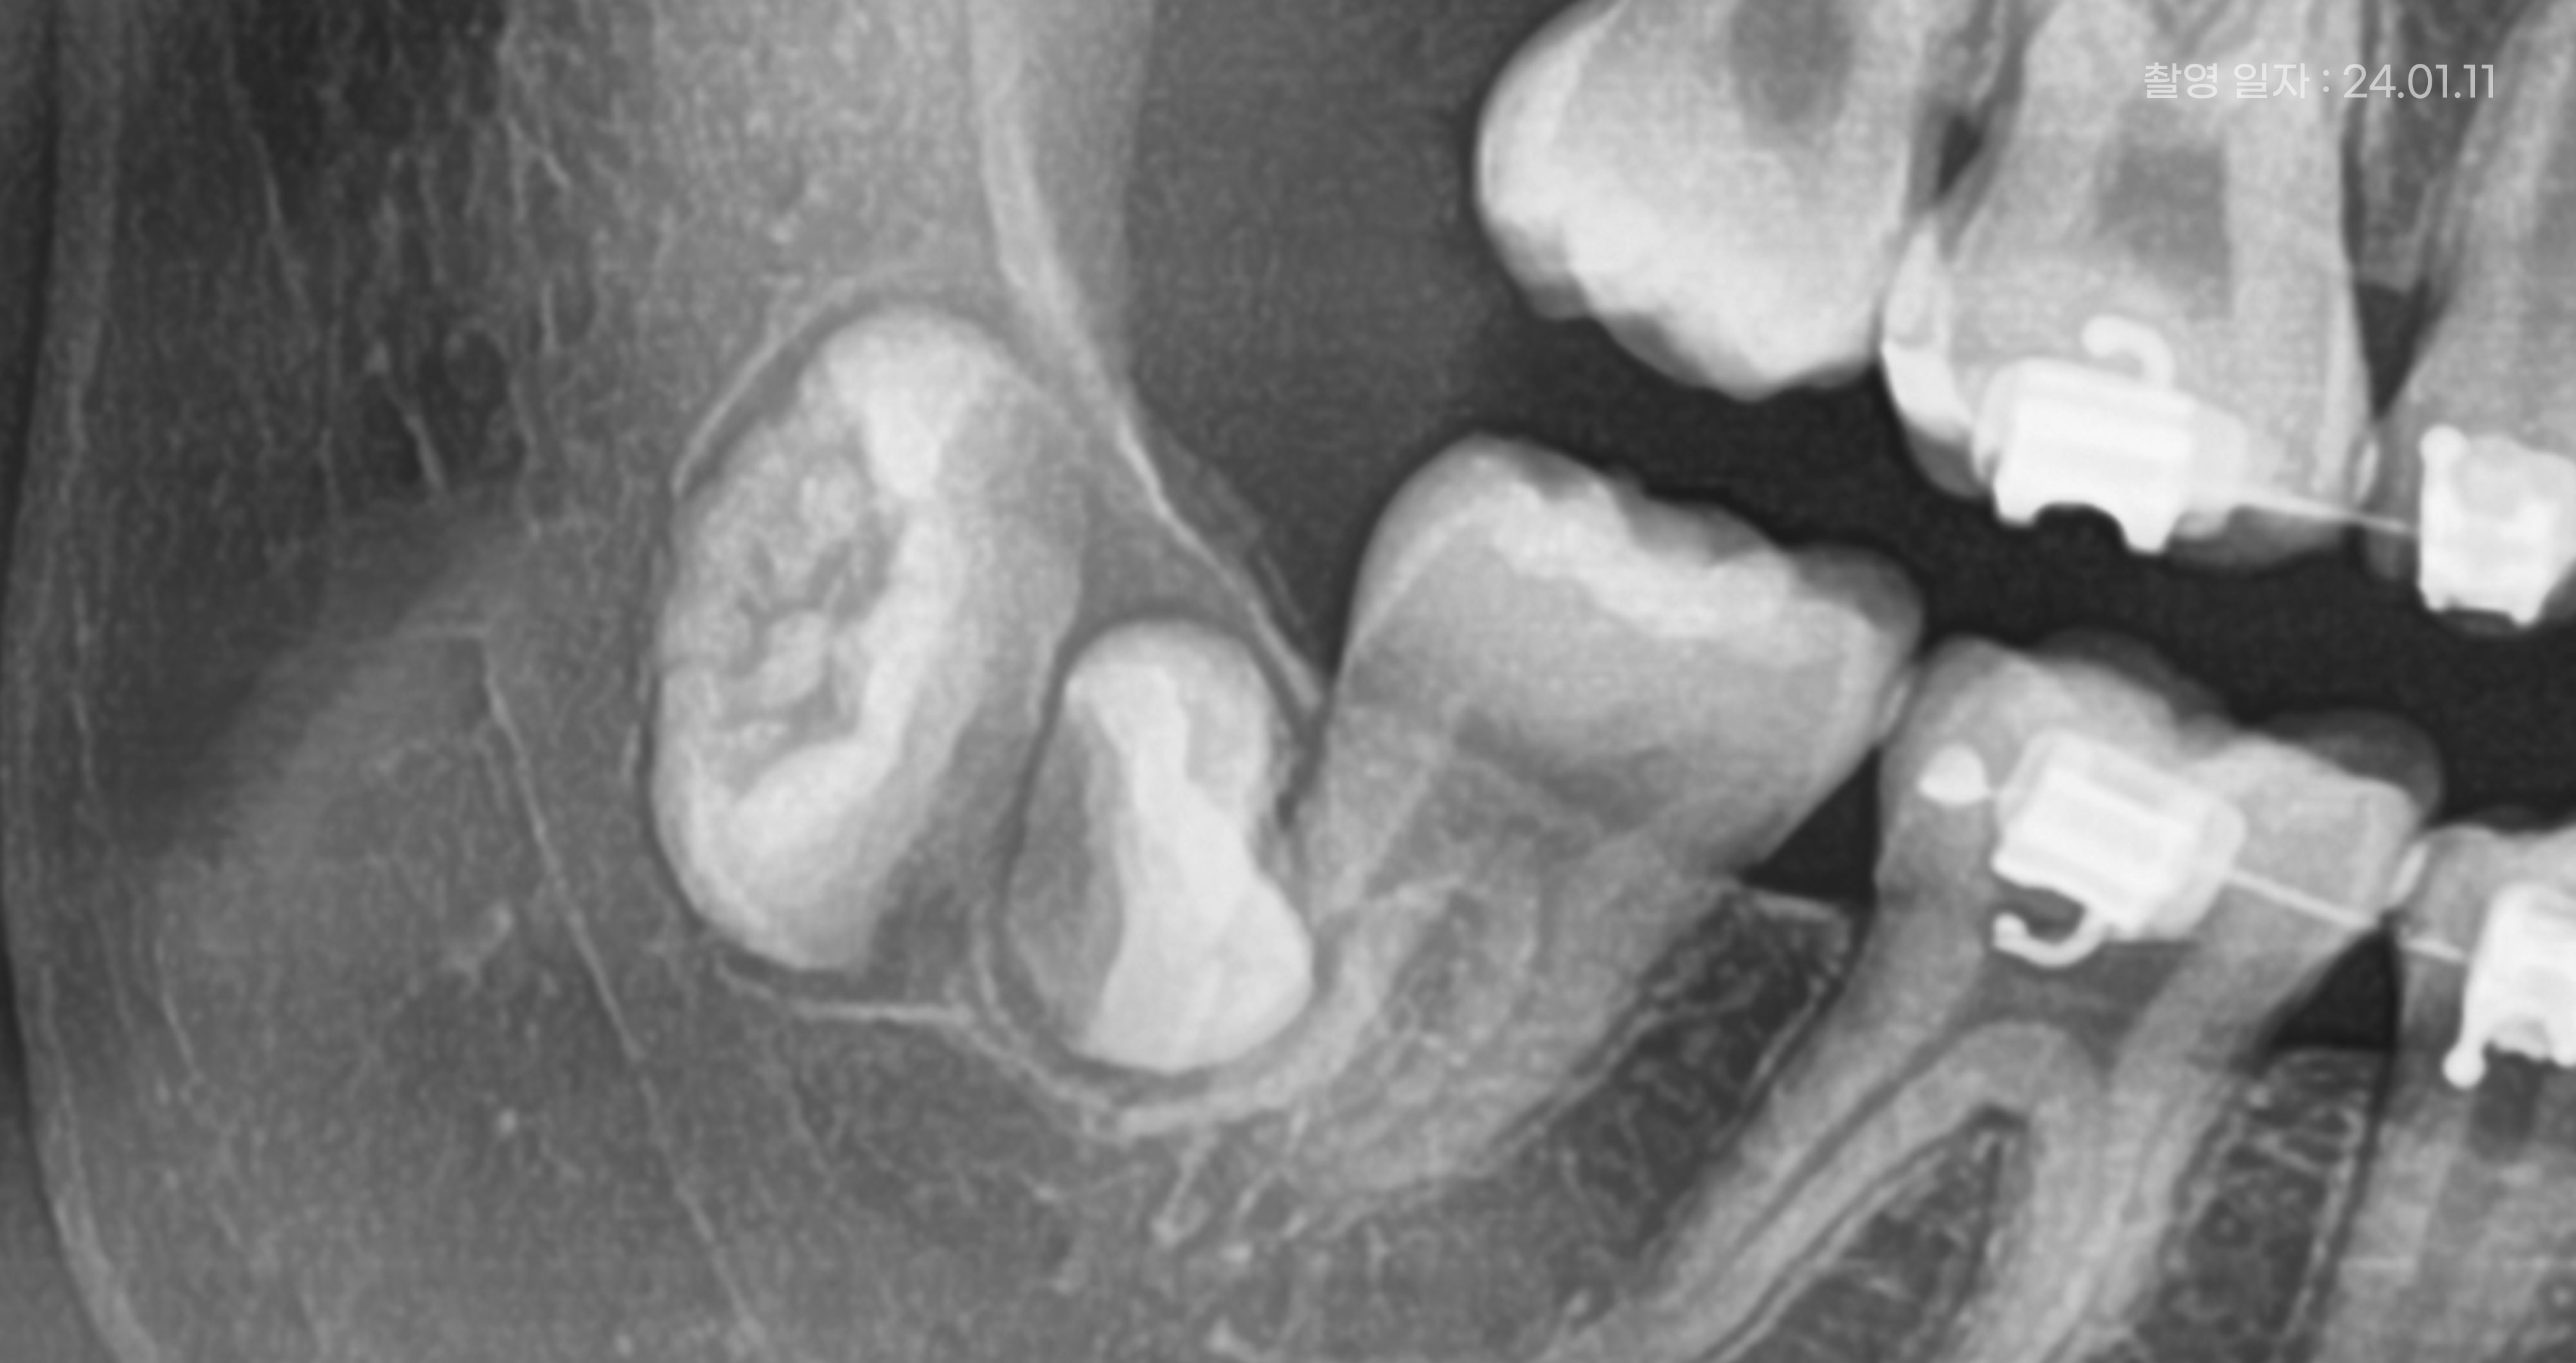

<매복사랑니 발치 전 예시 사진>

매복사랑니란, 말그대로

잇몸 속에 묻혀 있는 사랑니를 말합니다.

특히, 매복사랑니는 잇몸 속에 묻혀 있어

더욱 관리가 어렵습니다.